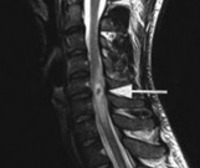

• МРТ спинного мозга и головного мозга. МРТ с контрастом определяется как утолщение мозговых оболочек, симптомы гидроцефалии (желудочковая асимметрия, расширение первичных резервуаров), полиморфные гранулемы с четкими контурами, периорбитальный отек и хорошее накопление контраста.